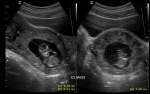

Clinical findings: on clinical assessment. she was hemodynamically stable. Ultrasound scan showed a live CEP at 12 weeks + 1-day gestation, with the complete invasion of both cervical lips, and vascularity under Doppler color interrogation (Figure 1, Figure 2, Figure 3). Baseline laboratory results showed a hemoglobin concentration (Hb) of 12.6 g/dl, negative sickle cell screen, blood group of B Rhesus positive, and high serum β-HCG of 126,750 Miu/ml.

Figure 2: two transabdominal ultrasound images showing live cervical ectopic gestation: A) fetal pole with a Crown-rump length of 5.62 cm and a gestational age of 12 weeks+1 day; B) mass completely invaded both cervical lips and shows vascularity under Doppler color interrogation, fetal heart vascularity is seen